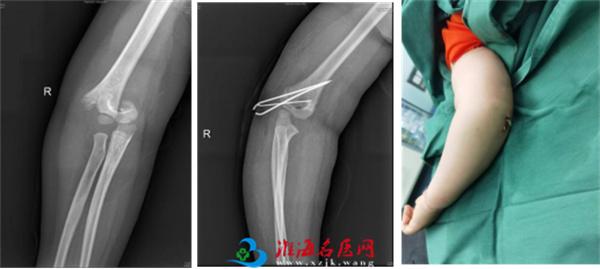

小儿骨科依托省级临床重点专科骨科平台,拥有雄厚的医疗、科研实力,配备了脊柱手术显微镜、术中导航、脊柱微创内镜、关节镜设备、术中神经电生理监测、超声骨刀等先进设备,极大地保证了患儿高难手术的精准性和安全性。自2022年2月17日成立以来,小儿骨科秉承“微创化、精准化”的治疗原则,为淮海经济区儿童骨科患者提供优质的医疗服务,赢得了广泛赞誉。当前,小儿骨科每月完成手术近40余台。小儿肱骨髁上骨折、前臂骨折、股骨干骨折等常见骨折基本上都是经皮微创完成,获得患儿家长的好评和信任。